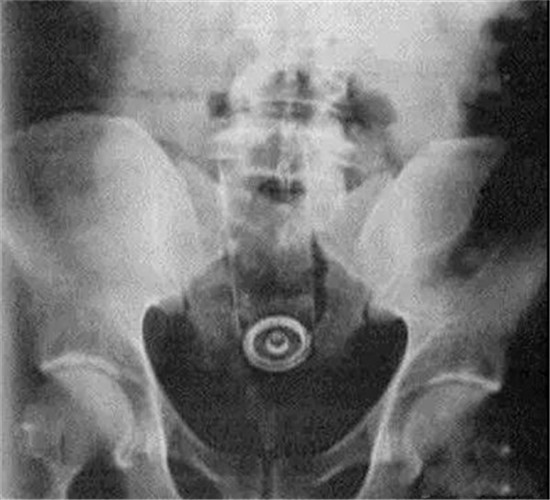

类似的还有圆形的球类的异物。

这是一个直径8厘米的玻璃圆球。

直肠里塞了灯泡或者圆球,是肛门自慰人群的常见意外。

要取出灯泡,需要肛门充分松驰,才能取出来。可以在肛门处打局麻,但是效果不好,不够松,可以打腰麻或者硬麻,当然,最好是全麻,就可以有满意的肛门松驰。

其次,就是选用合适工具。

上面图片是产钳,从直肠里把直径8厘米的圆球拽出来。

只要产钳能够夹住灯泡或者圆球,把肛门扩大,可以轻松把灯泡拽出来。不用担心灯泡会碎了。当然,为了保险起见,可以在直肠与肛门处打 润滑油如石蜡油,有润滑后,会更容易拽出来。